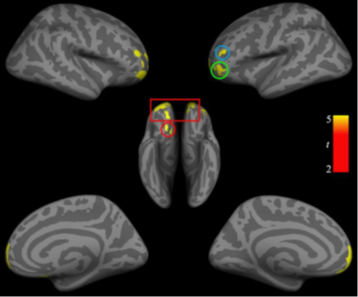

发表在《Brain Imaging and Behavior》上的论文采用分析了26个英雄联盟(LOL)玩家和26个非玩家的大脑结构差异。这些LOL玩家每天至少玩3小时以上,平均具有8年以上的视频游戏经验。数据分析采用了时下最流行的Cat12,VBM结果发现LOL组双侧腹侧前额叶皮层和左背外侧前额叶皮层以及左侧顶叶小叶的灰质体积小于控制组,随后DBM分析、皮层厚度分析和脑沟深度分析都印证了这些结果。

图1:VBM结果发现LOL组在前额叶皮层区域具有较低的灰质体积